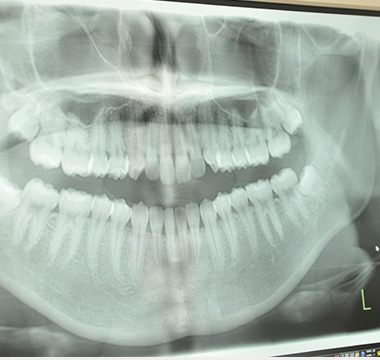

歯科用デジタルレントゲン(オルソパントモ)を使用し、顎の全体像を一度に撮影するため、精密な診断を行うことができます。